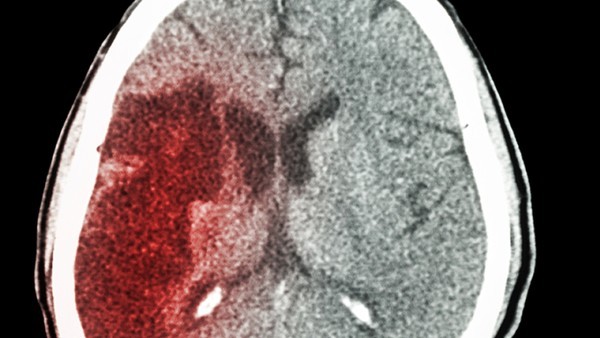

除了利用药物治疗脑积水我们还通过手术去进行调理。只有到了非常严重的情况之下我们才考虑利用手术来进行治疗。减少我们脑部的脑脊液的分泌,或者是利用脑脊液的分流术来进行治疗。

脑脊液分流术:对不能纠正病因且药物治疗效果差者,可根据病变情况及阻塞部位选用脑脊液颅内或颅外分流术,颅内分流术常用脑室-小脑延髓池引流术及三脑室造瘘术等。颅外分流术中目前疗效以脑室-心房分流术及脑室-腹腔分流术为好,但有感染及再阻塞的可能。都可以达到脑积水的治疗效果,但是要选择正确的方法。